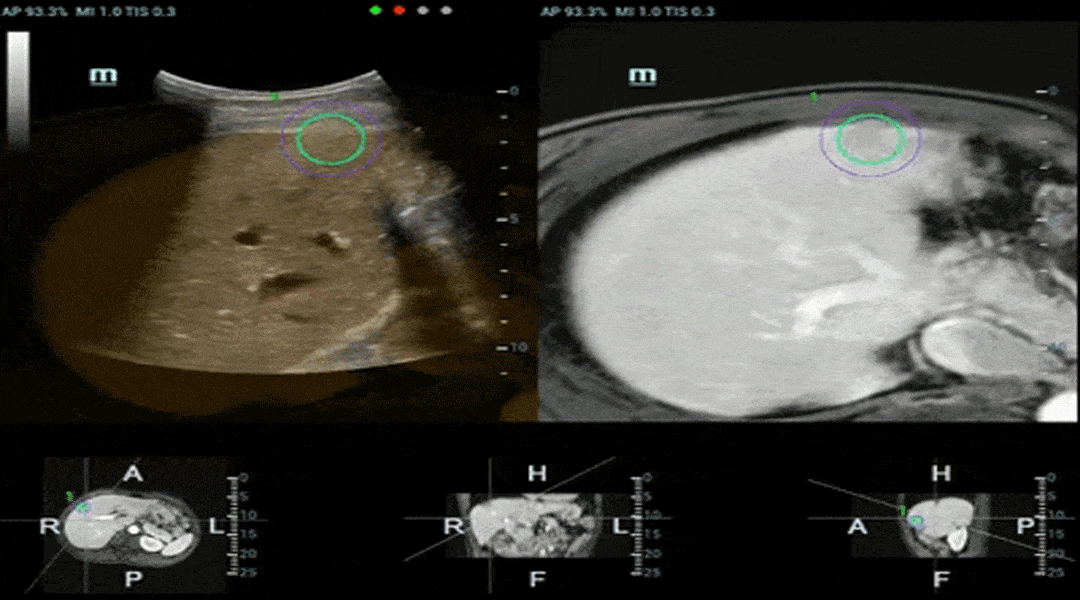

pc68-s4

3D sphere target marker on both CT/MRI and US images for easy lesion-targeting